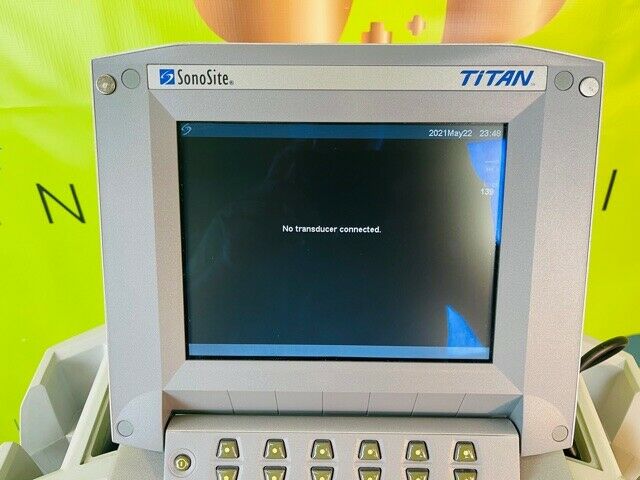

SONOSITE TITAN PORTABLE ULTRASOUND (w242)

Sale price$ 6,888.00